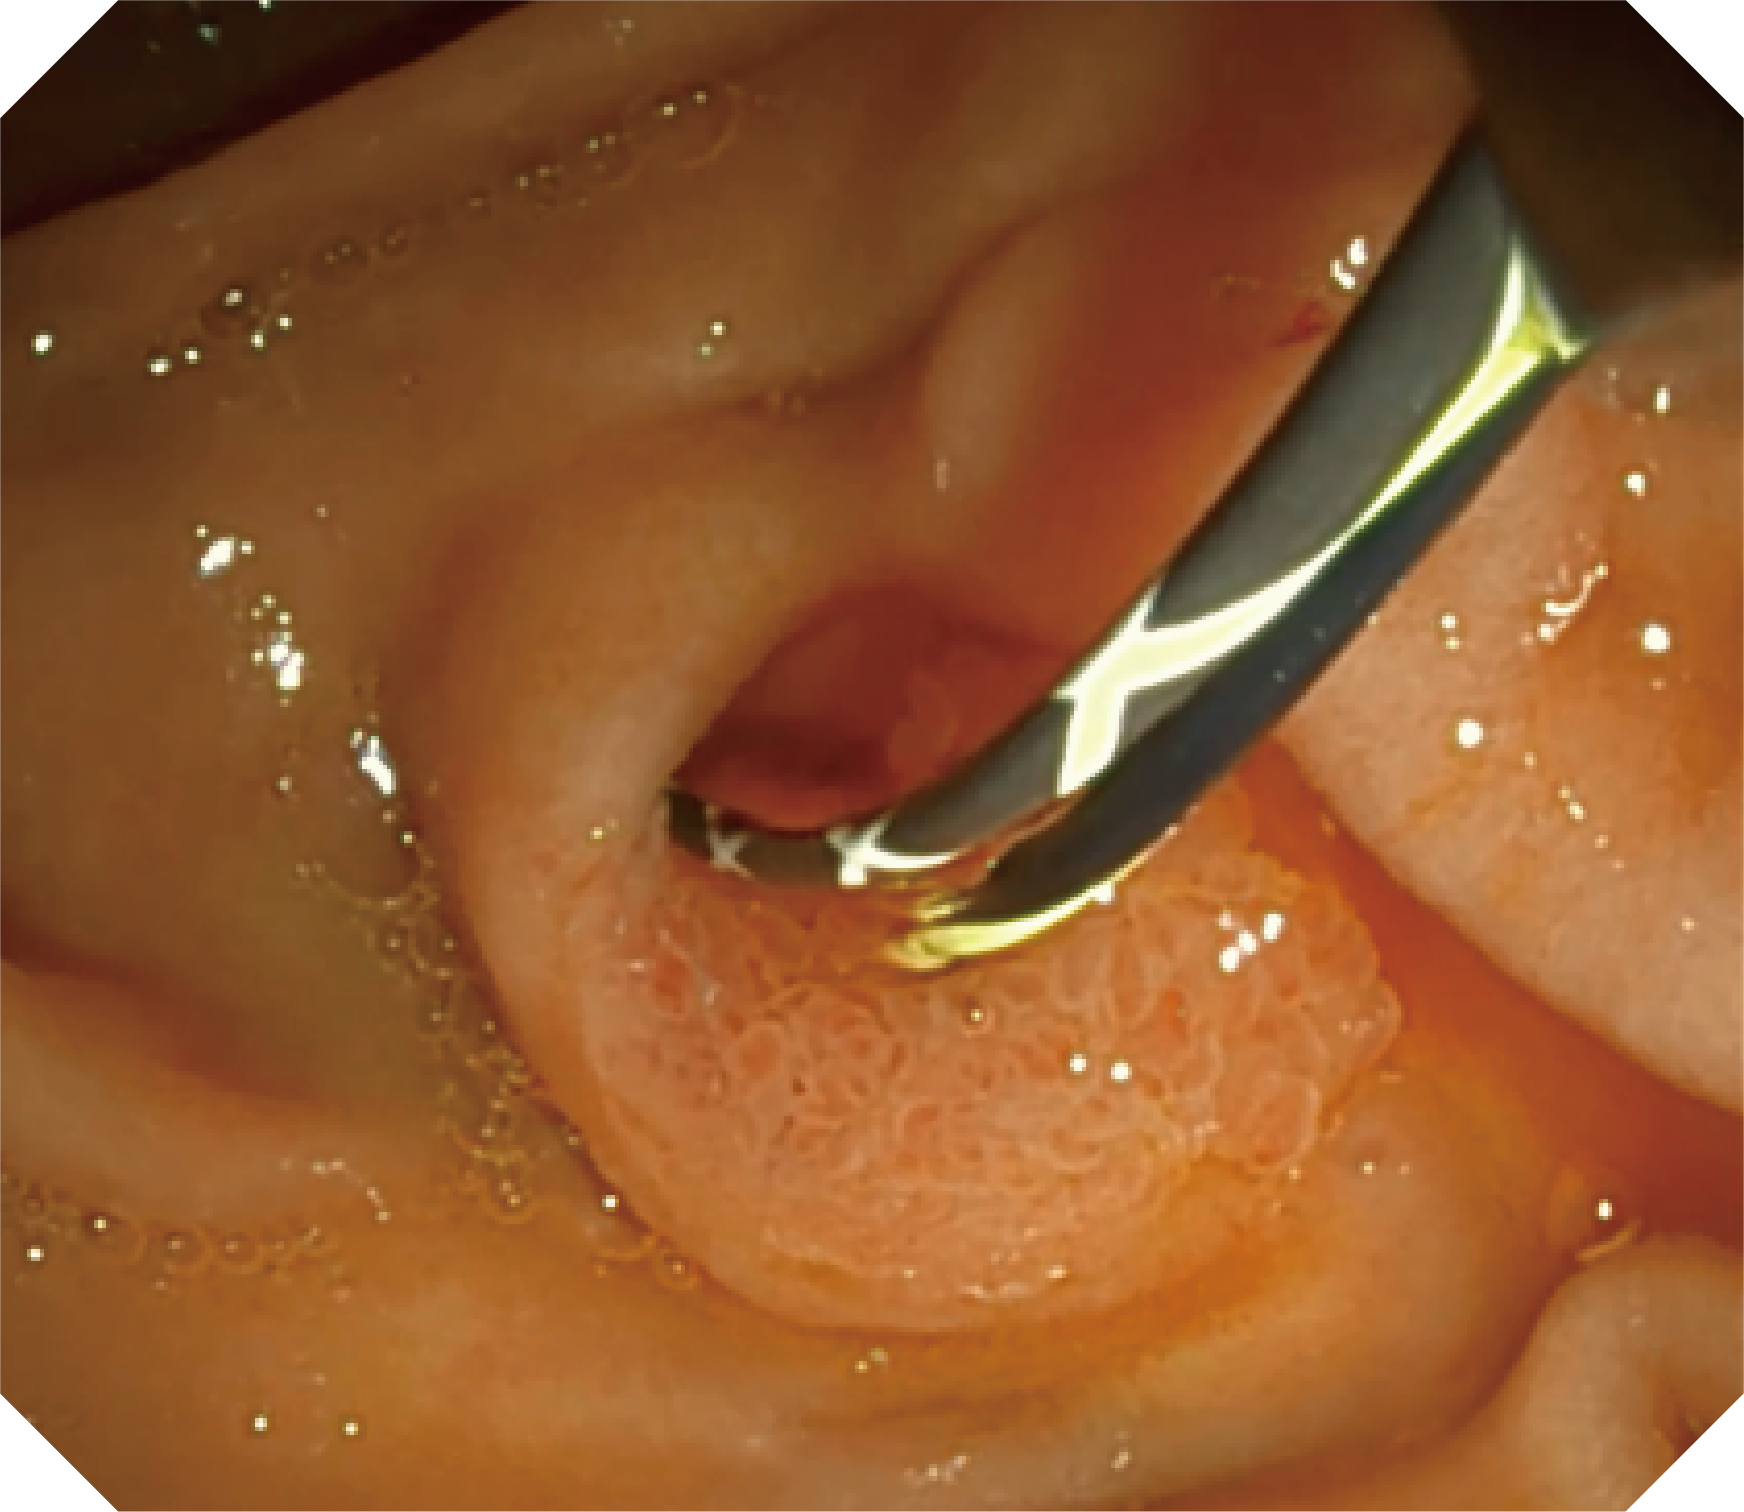

高清画质

CMOS传感器提供高清内镜视野 SFI/VIST光学染色技术凸显病变区域

• 器械辅助导向功能

当切开刀伸出视野外时,导向面引导其回归视野